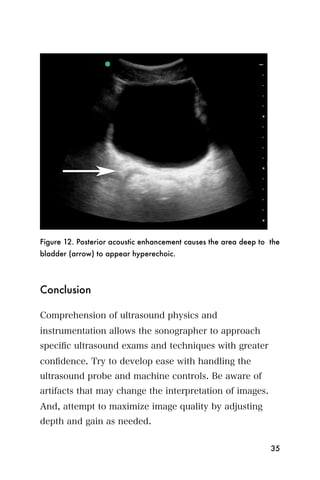

Posterior Acoustic Enhancement occurs when ultrasound

waves travel quickly through a low density medium,

such as urine in the bladder, and then reflect back

quickly from the next structure encountered that is

higher in density, such as the posterior bladder wall.

This causes structures deep to the hypoechoic object to

become falsely hyperechoic, and may require you to

adjust the gain.

Figure 12. Posterior acoustic enhancement causes the area deep to the

bladder (arrow) to appear hyperechoic.

Comprehension of ultrasound physics and

instrumentation allows the sonographer to approach

specific ultrasound exams and techniques with greater

confidence. Try to develop ease with handling the

ultrasound probe and machine controls. Be aware of

artifacts that may change the interpretation of images.

And, attempt to maximize image quality by adjusting

depth and gain as needed.